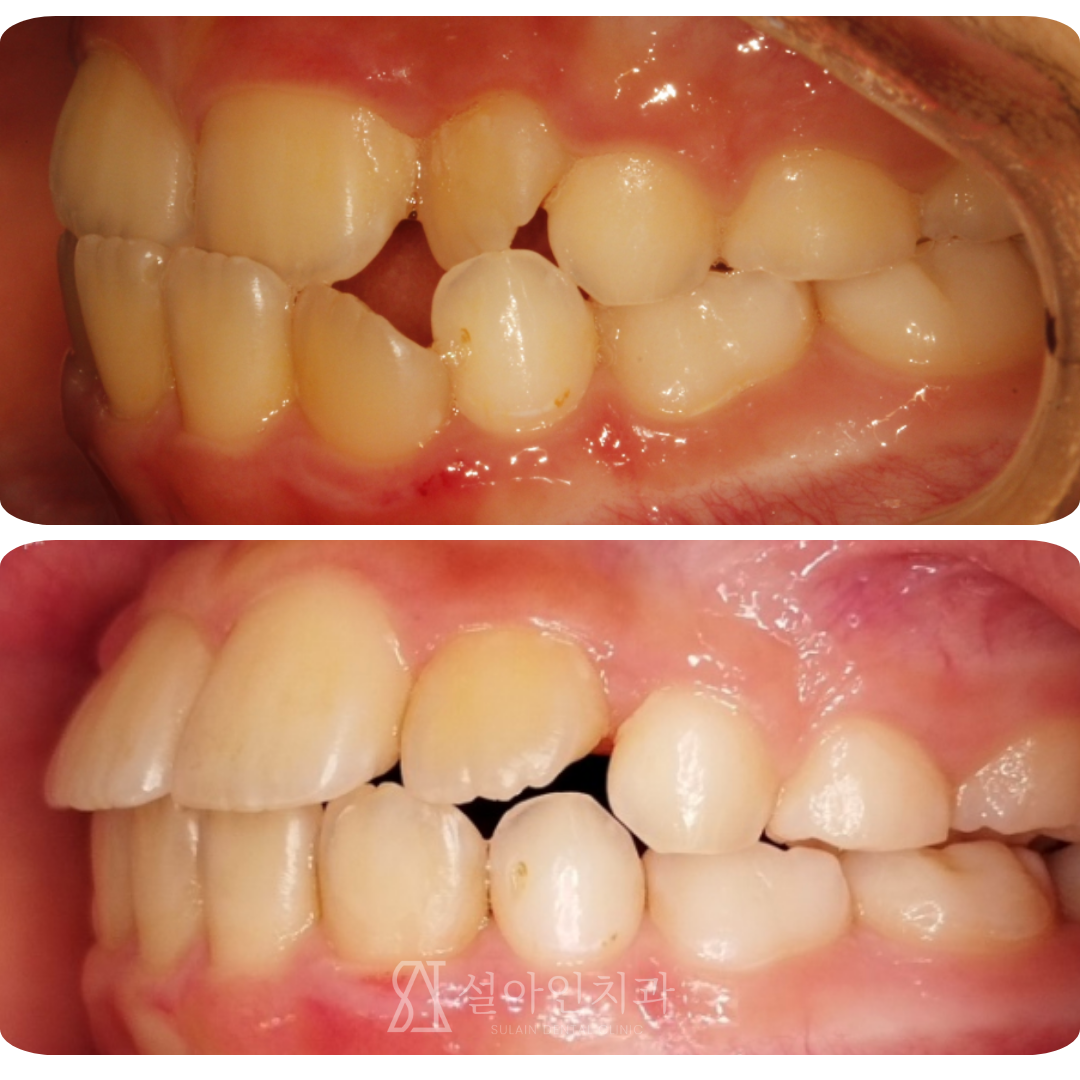

반대교합 어린이, 투명교정으로 아프지 않게 정상교합 만들기